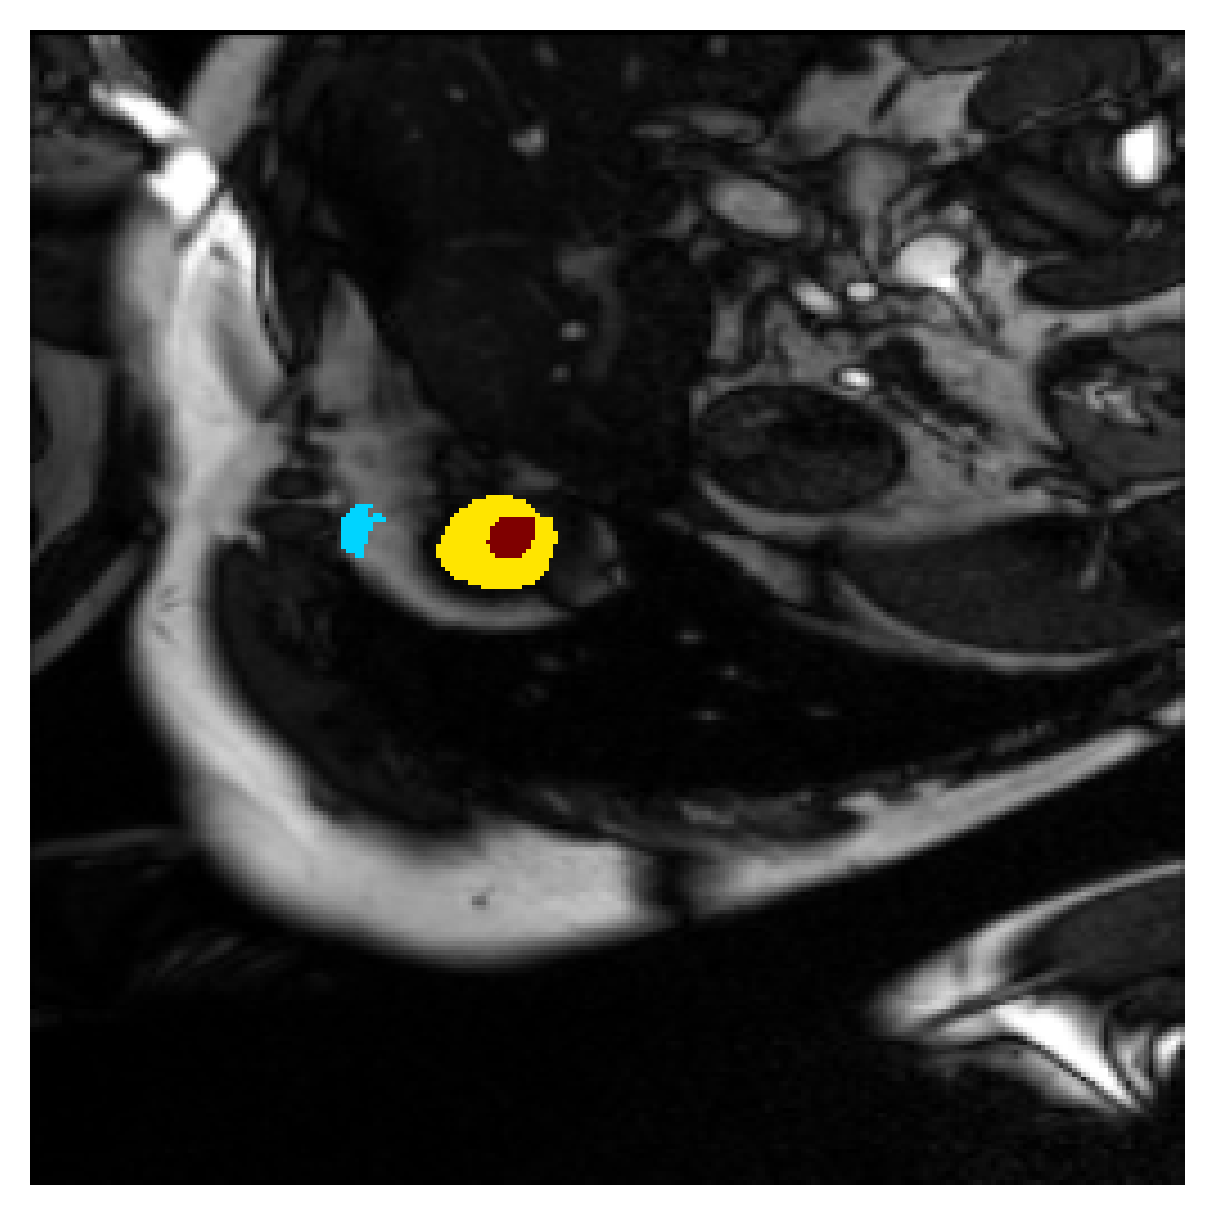

We normalize the volumes and resize the slices to pixels. As the official dataset comes with full annotations, we create a synthetic point ground truth. This is done by first randomly choosing the centers of the point annotations within the class masks, followed by filling an ellipse with axes lengths of and (in pixels) around each center. The intersections of these elliptic discs with the underlying full annotations are then used as our point ground truth. See Figure 2 for an example of the created weak annotation mask. The point annotations are created for every slice, one for each foreground object present in the slice.

Qualitative comparison

|

|

|||

|

|

|

|

|

|

|

|

|

|

|

|

| (a) Ground truth | (b) , full | (c) , weak | (d) |

| (full) | supervision | supervision | |

|

|

|

|

|

|

|

|

|

|

|

|

| (e) | (f) | (g) | (h) CRF-loss |

In Figure 6 we provide qualitative results on a number of randomly chosen test set slices. Upon visual inspection, we can observe that training with the intensity-aware distances (particularly with and ) follows the image gradients better and is better at recovering the underlying shape than the Euclidean version. The CRF-loss seems to recover the shape of the myocardium and left ventricle to some extent, but fails entirely on the right ventricle.